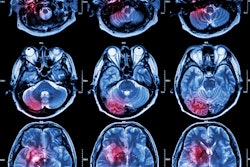

T1 maps generated after processing the field-cycling imaging scans in a 79-year-old male participant with right occipital lobe infarct. Images were processed with a total generalized variation regularization. The infarct, shown in yellow, demonstrates higher T1 relaxation time constant than the unaffected brain tissue. The infarct is clearly visible at 21.1 and 2.2 mT, where the infarct to contralateral tissue contrast ratio is higher (percentage difference in T1 of 12.3% at 200 mT, 46.6% at 21.1 mT, and 46.2% at 2.2 mT). The color bars indicate the T1 values in milliseconds. Images and caption courtesy of the RSNA.